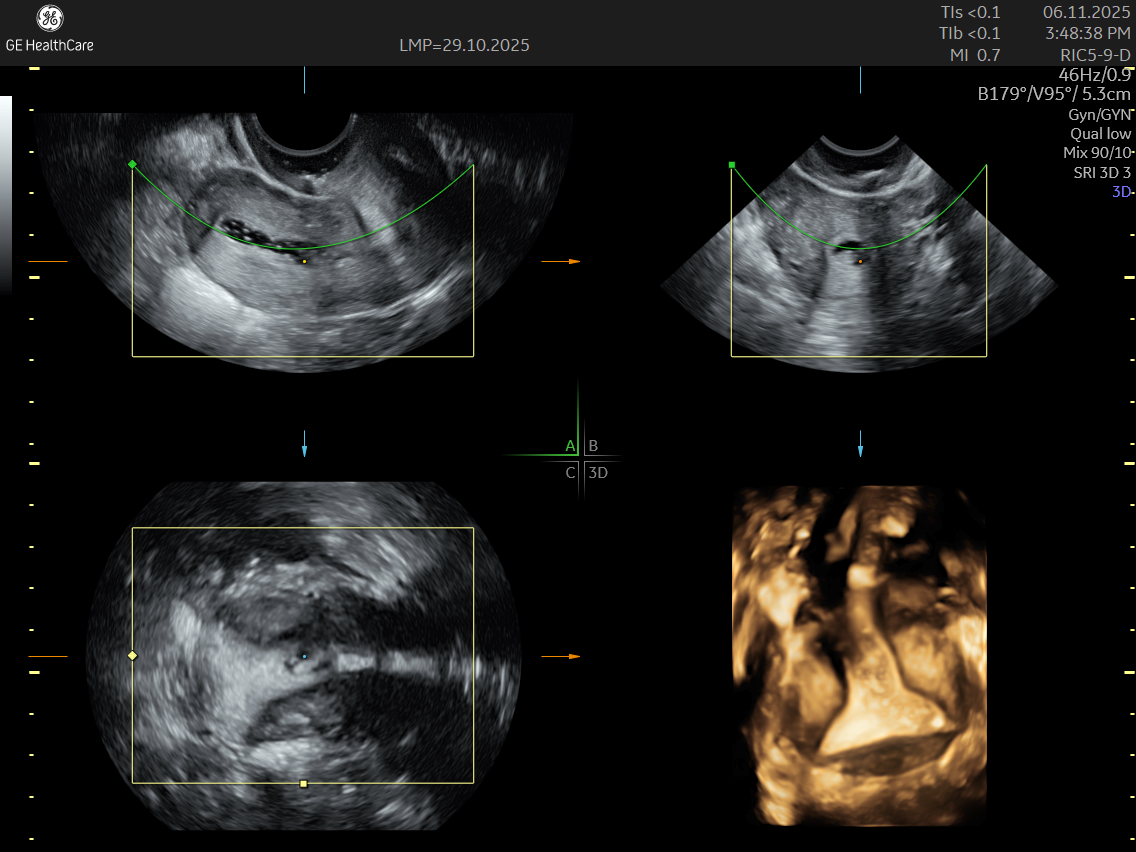

IMAGE GALLERY